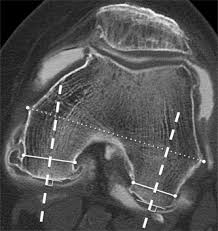

Figure 3 From Impingement Between Medial Plica Against Femoral Condyle Osteophyte After High Tibial Osteotomy Semantic Scholar

Figure 3 From Impingement Between Medial Plica Against Femoral Condyle Osteophyte After High Tibial Osteotomy Semantic Scholar from d3i71xaburhd42.cloudfront.net